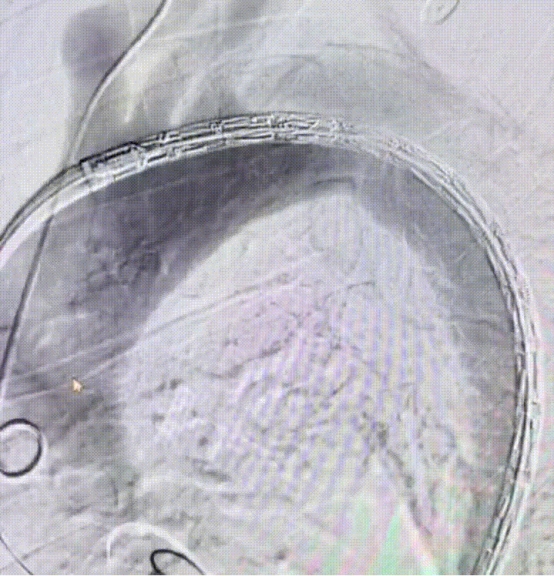

成功释放主体支架

成功置入分支支架,造影显示支架塑形良好,无内漏,LSA血流通畅